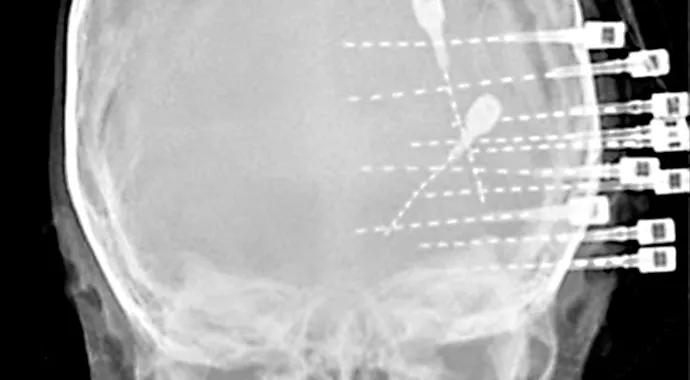

Figure 2. Skull X-ray demonstrating positioning of the SEEG electrodes. BB has remained seizure-free for more than 18 months since her surgery.